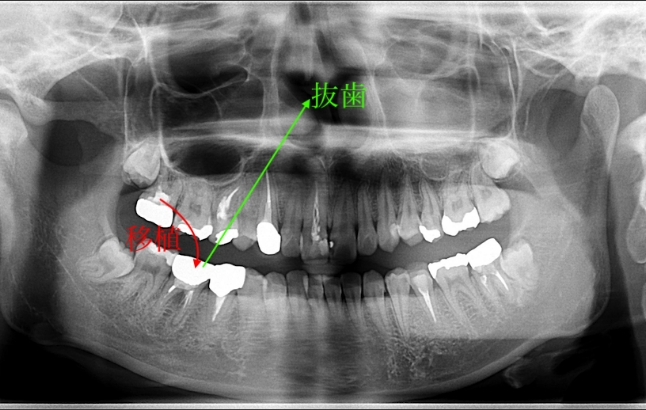

歯牙移植による右下部位の治療例

- 年代、性別 20代・女性

- 来院動機 他院で右下の歯を抜き、インプラントを勧められたが、歯牙移植ができないか相談したいと来院されました。

- 治療内容 右下の残せない歯を抜歯し、ご自身の不要な親知らずを取り出して、右下の抜歯部に移植しました。

- 治療期間 約2週間

- 治療費用 176,000円(税込)